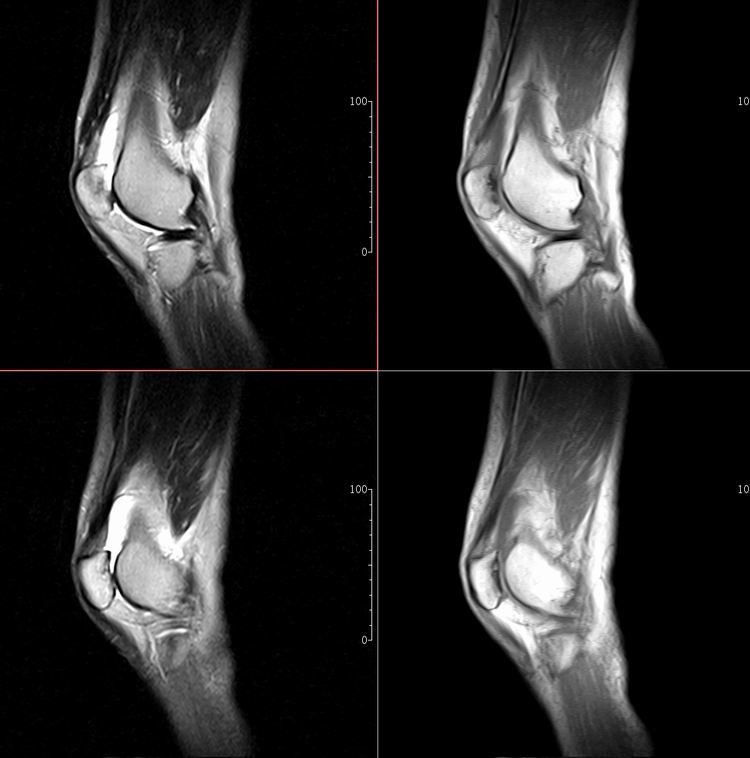

标题: MRI1910:M 687Y。近日因外伤疼痛,而就诊。

m 687y。近日因外伤疼痛,而就诊。有外侧副韧带损伤吗??因片子较差各位请包涵。

关节退行性变伴股骨外髁关节面下囊肿,不除外剥脱性骨软骨炎.关节积液,髌骨软化症

体位不标准。关节退变伴关节积液。

1)膝关节骨质退行性改变。

2)由于体位的关系不能确定有外侧副韧带的损伤。

关节退变伴关节积液,外侧副韧带的损伤

关节积液,外侧副韧带的损伤